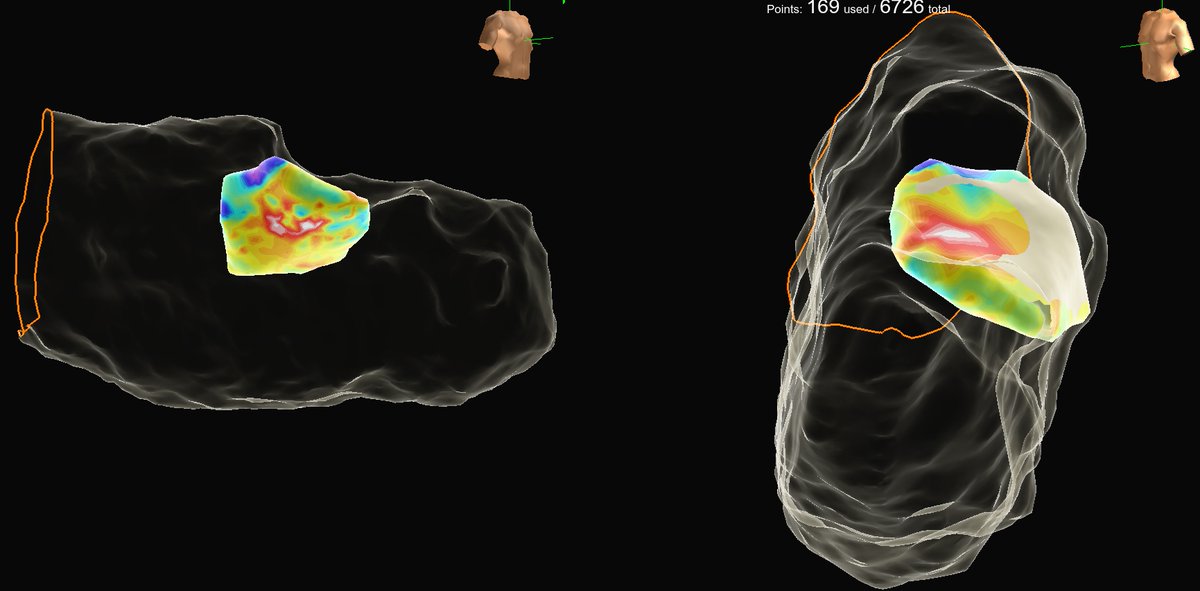

Volt released some pretty impressive 12 month data with over 80% success in paroxysmals and excellent persistent AF results. Read the simultaneous publication! kwnsfk27.r.eu-west-1.awstrack.me/L0/https:%2F%2…